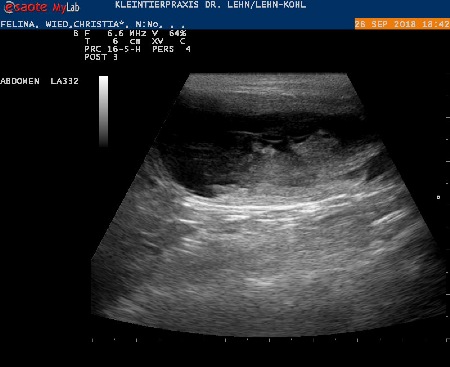

28.09.18 :

Wir waren beim Ultraschall ...Felina ist trächtig !!!